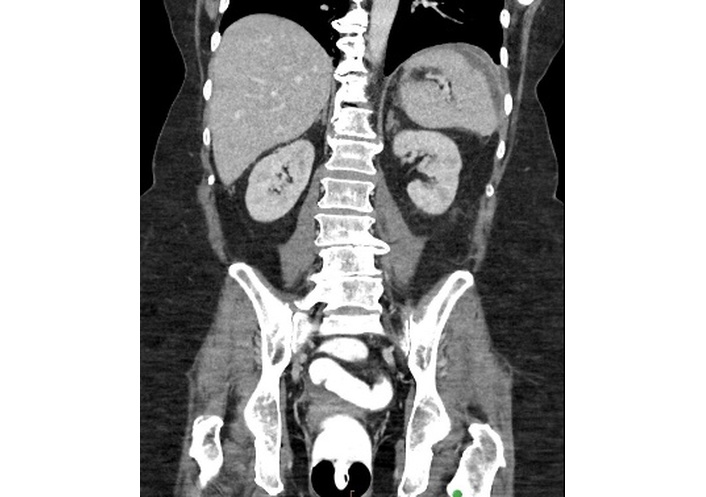

Due to limited access to general surgery care, the patient’s colonoscopy was delayed until 6.5 weeks after the initial presentation (34.5 weeks after IXE induction and 18.5 weeks after the onset of gastrointestinal symptoms), during which she experienced an additional 30-pound weight loss. Periprocedural labs revealed CRP 17.26 mg/dL and ESR 75 mm/hr. Once performed, the ileocolonoscopy report states the terminal ileum appeared normal, but the right colon displayed severe colitis, marked by pronounced erythema, friability, serpiginous ulcerations, and spontaneous bleeding. The sigmoid colon and rectum were reported as “relatively spared” (Figure 1). Histopathological examination of segmental biopsies obtained reported mild focal active ileitis and colitis without evidence of chronicity. Immunohistochemical staining for cytomegalovirus (CMV) was negative. IXE was discontinued, with the last dose administered 4 weeks prior to ileocolonoscopy.

Ileocolonoscopy findings: (A) severe inflammation at the appendiceal orifice, and (B) hepatic flexure with (C) normal-appearing rectum visualized in retroflexion.